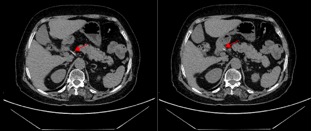

由于十二指肠球腔空间狭小,且镜子的稳定性差,内镜下直接取异物操作难度极大,一旦直接切开,进入腹腔内寻找异物,有引起迟发性穿孔的可能,需再追加外科手术,而该部位外科手术难度高,甚至需行胰十二指肠切除术(Whipple),创伤极大,为了避免上述并发症的发生,最终,魏志另辟蹊径,创新性地采用了内镜下经隧道肌切开异物取出术(手术过程-图4),首先于幽门前区前壁进行粘膜下注射,建立倒T型隧道开口,后逐层分离粘膜下层建立隧道至幽门口,浅切开幽门口环形肌至十二指肠粘膜隆起处,最终发现异物尾端。使用活检钳精准夹持,缓慢而平稳地将其完整取出——竟是一根长约3.3厘米的尖锐鱼刺(图5),用金属夹封闭隧道口,整个手术时长仅约30分钟,术后留置鼻胃管,禁食2天,刘阿姨的腹痛与便血症状消失,无术后并发症,复查腹部CT未见异物残留,恢复状况良好,顺利出院。

图4手术过程:a.建立隧道;b.发现异物尾端(红色箭头);

c.活检钳精准夹持异物(红色箭头);d.封闭隧道口